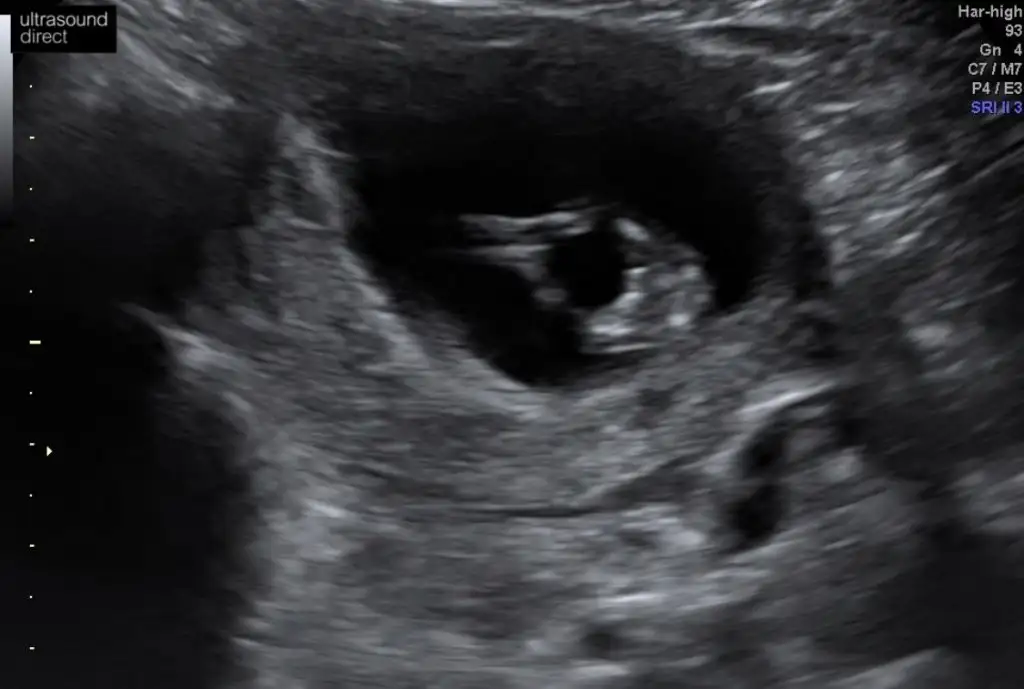

Anket Nub teorosi dogru tahminmi arkadaşlar

Nu teorisi dogrumu yanlışmı

• Tahminim dogrumu

OY: 357 76,6%

• Tahminim yanlışmı

OY: 109 23,4%

• Ankete Katılan

466

Valla dün 15+0 dı doktor hala yüzde yüz kız demedi 80 diyor:) ama zannetmiyorum değişeceğini daha öncede kız gibi demişti başka bi doktor